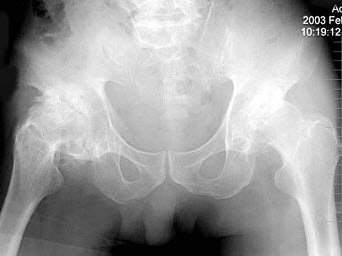

156、单项选择题

右髋关节疼痛,跛行1年多,无明显外伤史,双髋关节摄片如图,最可能的诊断是()

A.右髋关节退行性关节病

B.右髋关节创伤性关节病

C.右髋关节结核

D.右髋关节化脓性关节炎

E.右髋关节神经性关节炎